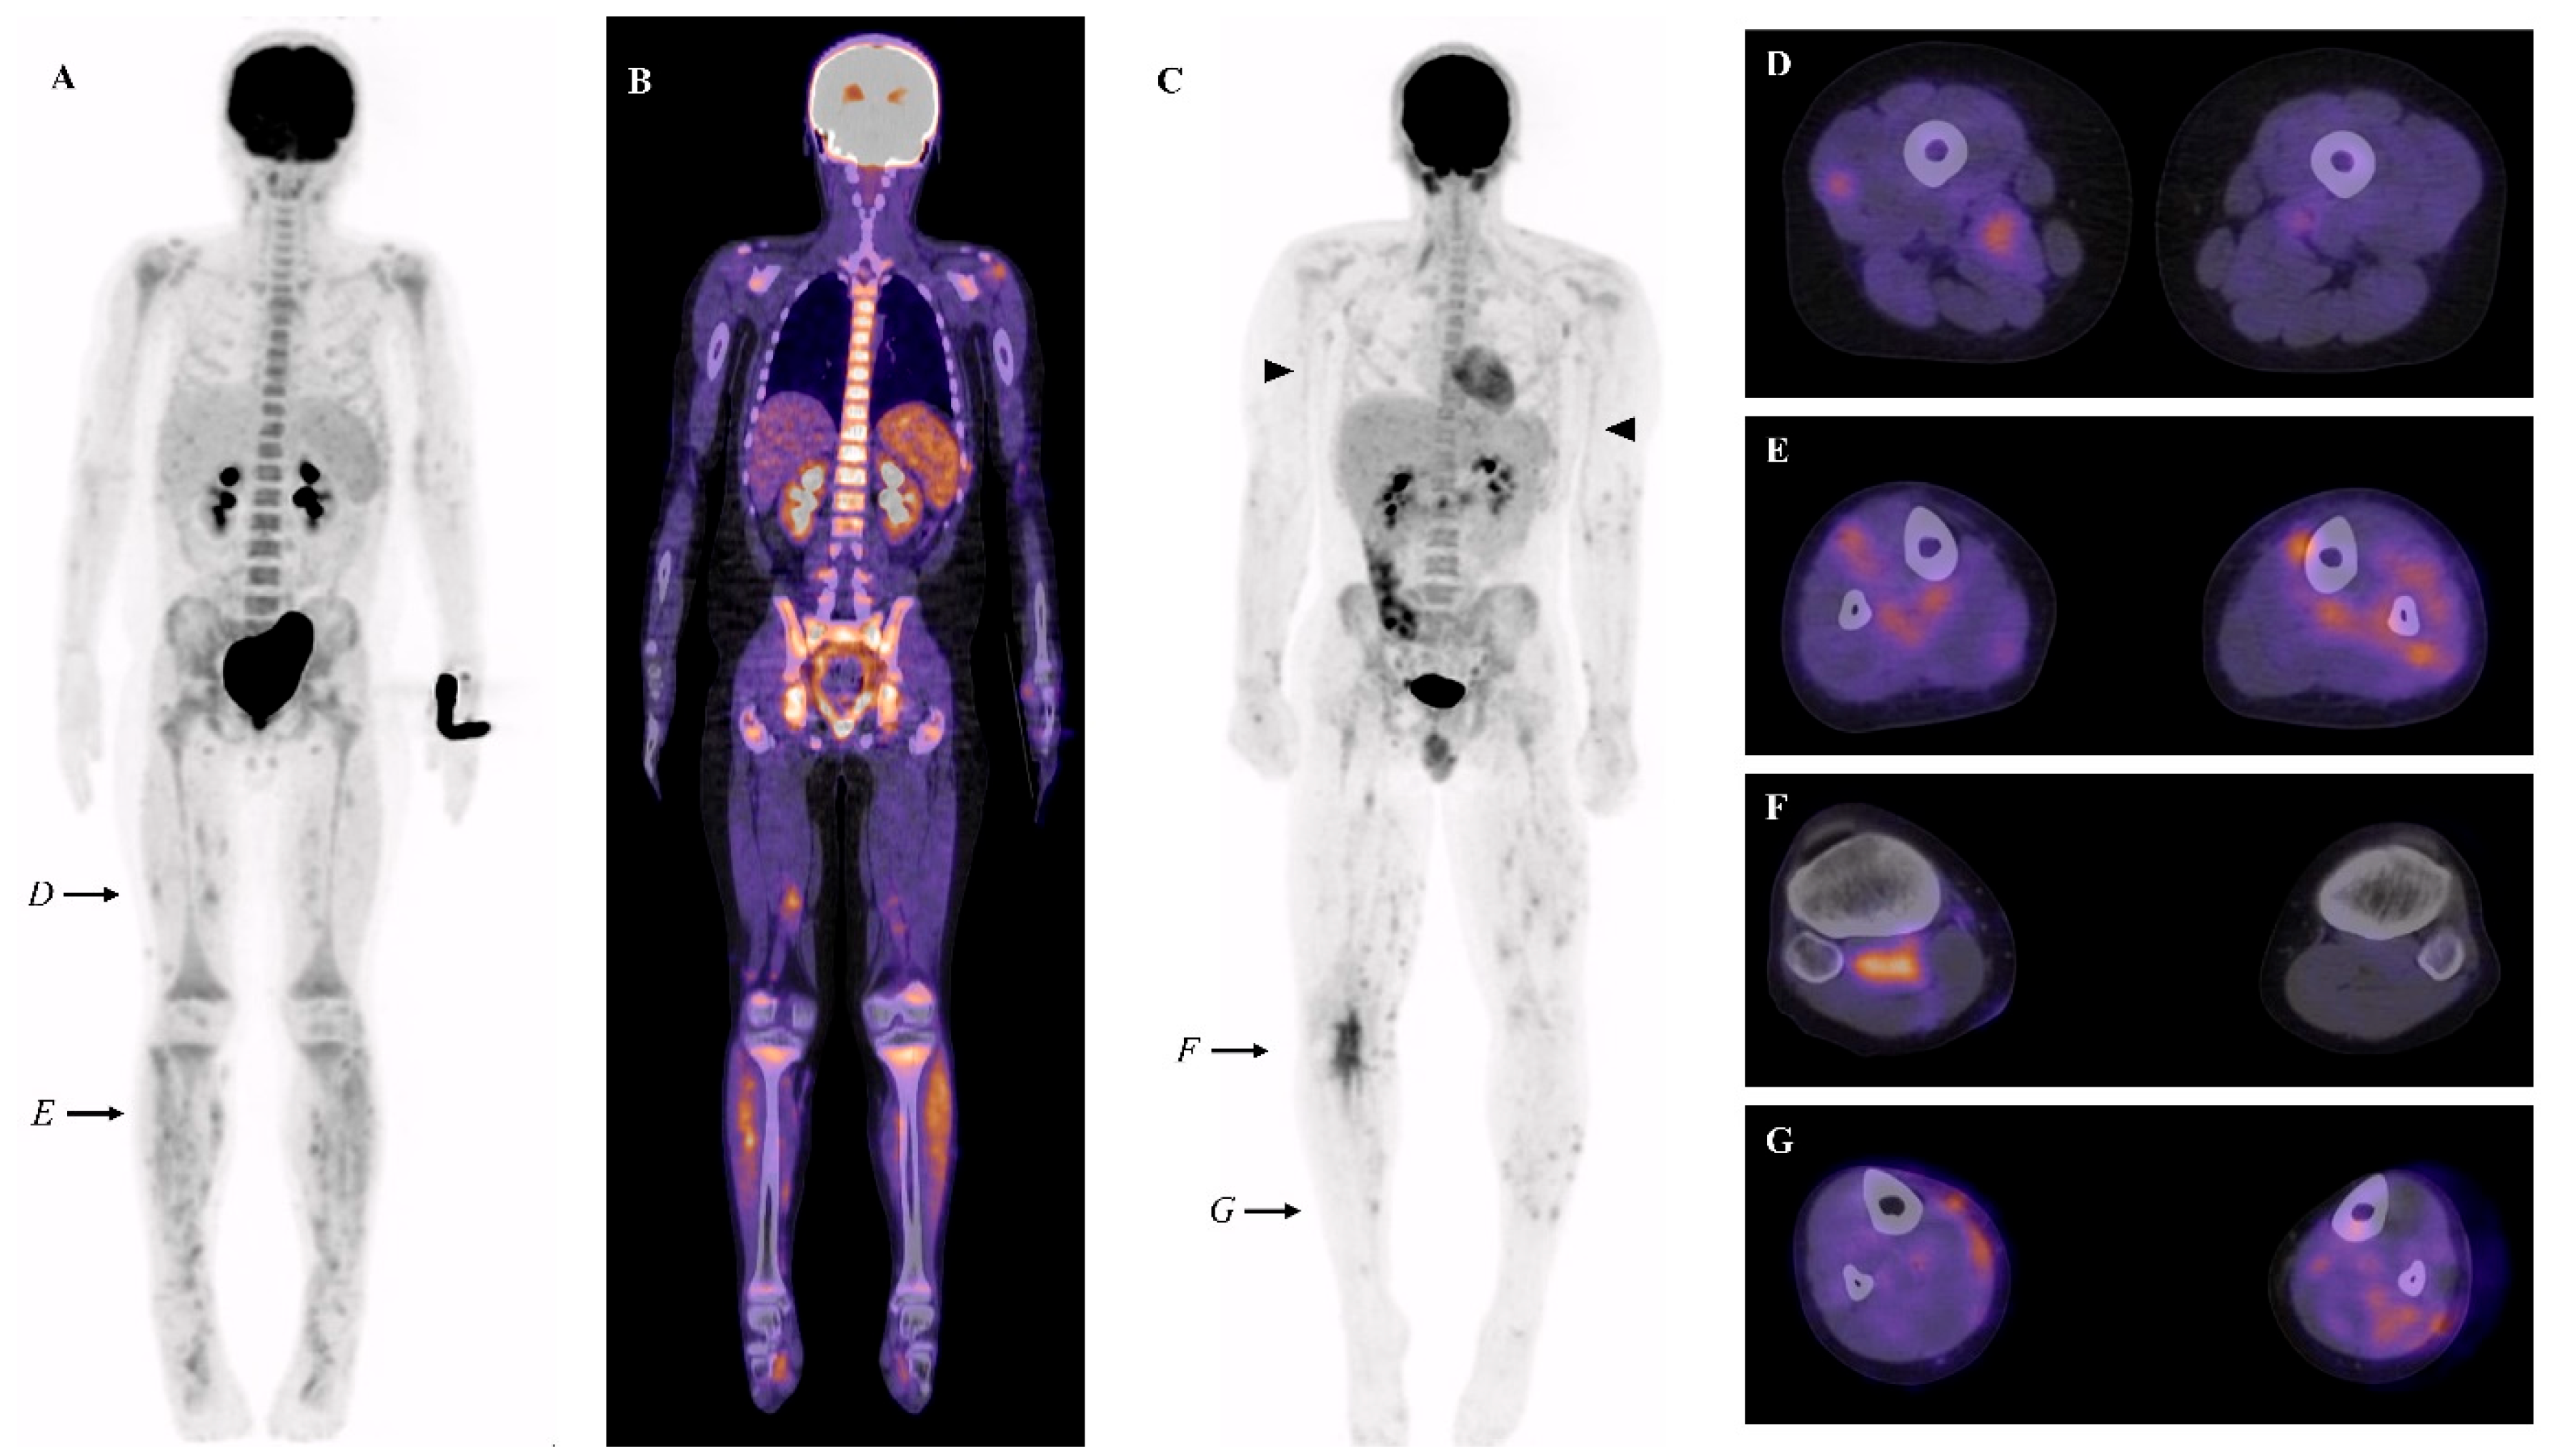

3.2. PET-CT (±MRI) Findings in Juvenile Onset PAN

PET-CT findings of each patient are summarized in Table 1. We found focal heterogeneous muscular FDG uptake in 4/6 patients, with a symmetric distribution (Figure 1A–G). In the same four patients, cutaneous/subcutaneous hypermetabolic foci were also present (Figure 1G). These findings were predominant in the muscles and skin of the lower legs. When numerous, a combination of these abnormalities can result in the so-called ‘leopard skin’ sign (Figure 1A). The intensity of the muscular and cutaneous/subcutaneous hypermetabolism was moderate (SUVmax ranging from 2.2 to 4.7). In addition, increased FDG uptake in large vessels (brachial arteries) was found in 1/6 patients (Figure 1C).

Figure 1. (A,B) Maximal intensity projection (MIP) (A) and representative fused FDG PET-CT coronal view (B) of patient 1, showing diffuse hypermetabolic foci in the lower limbs. (C) MIP FDG PET-CT of patient 2, showing diffuse hypermetabolic foci in the lower limbs, vascular uptake in both brachial arteries (black arrowhead), and the right popliteal region. (DG) Fused FDG PET-CT transverse views showing foci of increased muscular and subcutaneous FDG uptake in patients 1 and 2 (levels of the cross-sectional views are shown by black arrows in (A,C)).

We also found nonspecific, inflammation-related findings: hypermetabolic lymphadenopathies in 4/6 and splenic/medullary/thymic hypermetabolism in 6/6 (Figure 1B). These were the only abnormalities present in 2/6 patients. We found no association between clinical or biological features and PET-CT patterns.